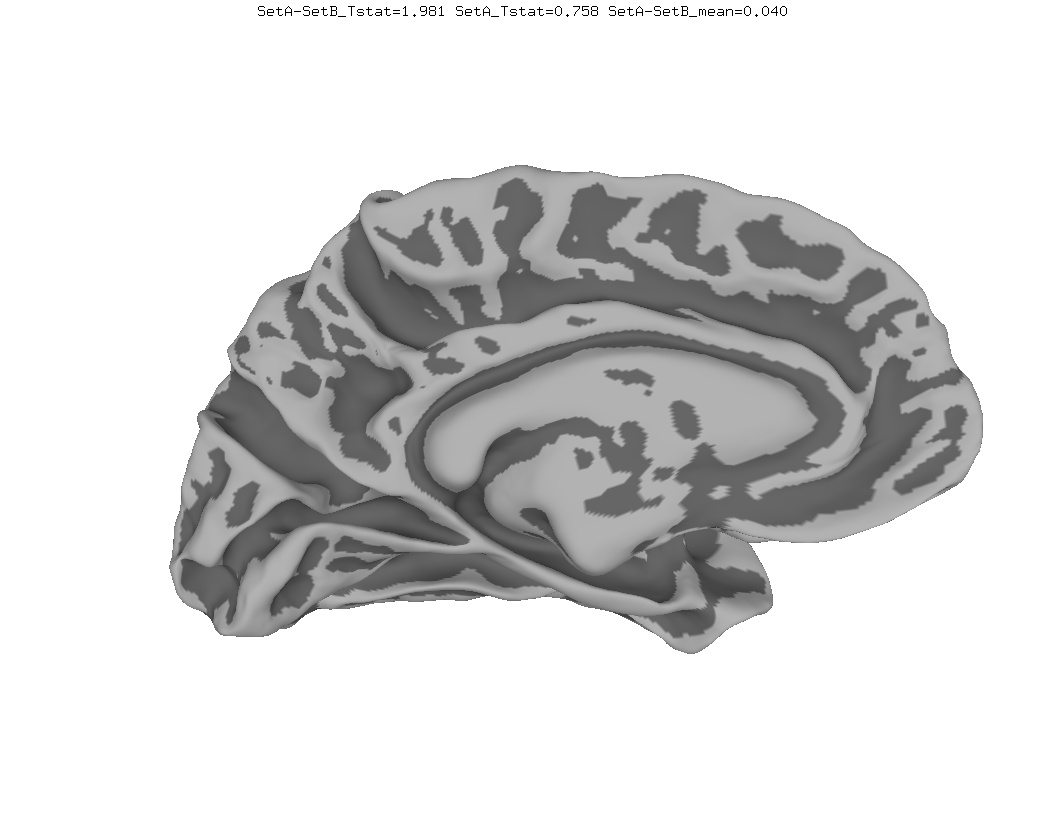

Functional Data

Functional data of the Mouth vs. Eye contrast mapped to the average surface. It is hard to quantify the difference, but one way is to compare the maximum statistical values; with better intersubject alignment, these would presumably increase.

- NEW: Max t-value for Mouth: 9.3 Eye:10.1 Eye vs Mouth: 5.6

- OLD: Max t-value for Mouth: 7.9 Eye:8.8 Eye vs Mouth: 5.8

data from Zhu LL, Beauchamp MS. Mouth and Voice: A Relationship between Visual and Auditory Preference in the Human Superior Temporal Sulcus. Journal of Neuroscience 8 March 2017, 37 (10) 2697-2708; DOI: https://doi.org/10.1523/JNEUROSCI.2914-16.2017. Click here to download the PDF. Surface averages were not used in this paper so the bug did not affect the published results.

New

Old